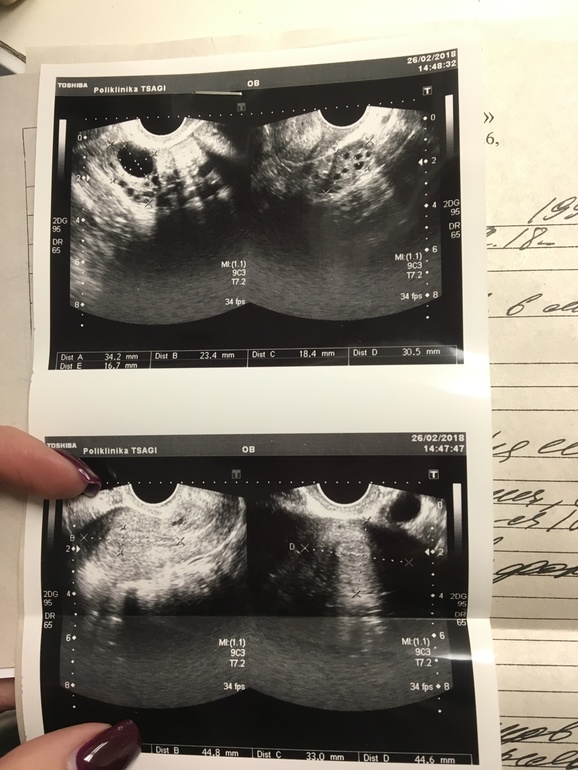

Фотка внизу прикреплена.. Переживаю, стоите получилось в этом месяце( Уже любые причины ищу Вот УЗИ ещё В том месяце была ановуляция.. А малыша хотим(